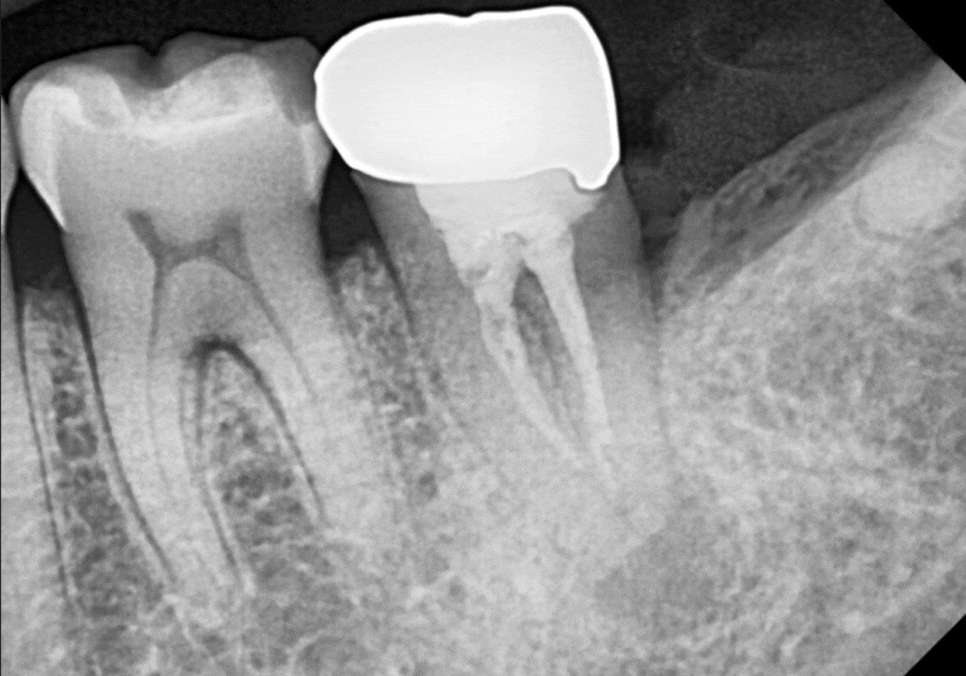

하지만 엑스레이 사진을 찍어보니

치아 뿌리 끝부분에

까맣게 나타나는 영역이 보이시나요?

250508

뿌리 끝에 염증이 생겨 주위 뼈가 녹아내리면

방사선상에서 저렇게

까만 그림자처럼 나타납니다.

환자분이 느끼셨던 욱신거림은

잇몸 뼈 안에서 염증이 보내는 신호였던 것이죠.